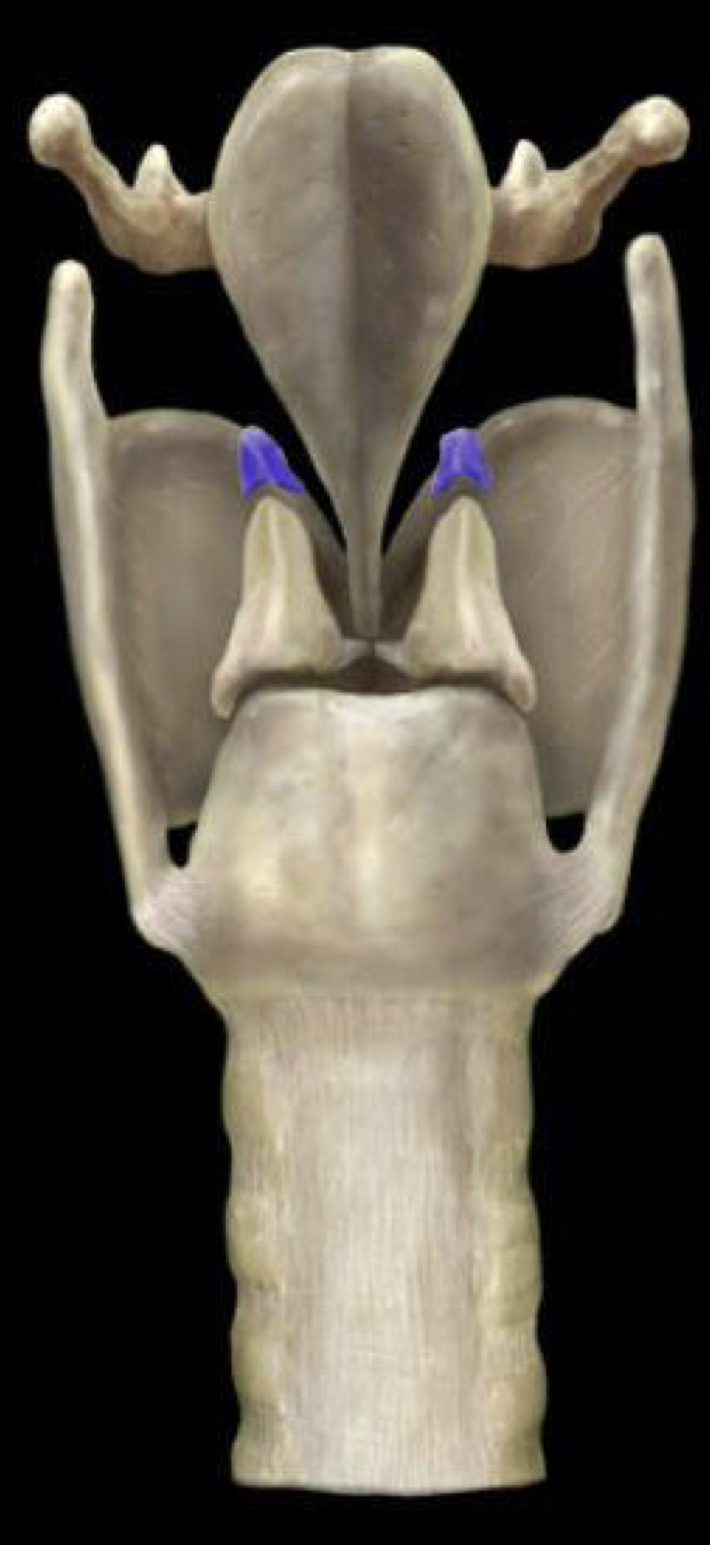

Arytenoid cartilage

Corniculate cartilage

Cricoid cartilage

Epiglottis

Thyroid cartilage

Trachea (larynx)

Tracheal cartilage